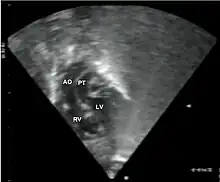

Additional images

Abbreviations: LV and RV=left and right ventricle, PT=pulmonary trunk, VSD=ventricular septal defect, PS=pulmonary stenosis.